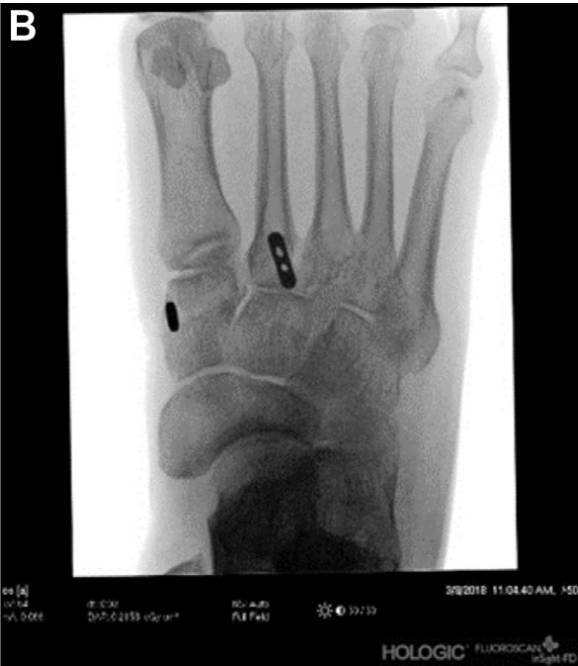

▲图示使用C臂机透视最终确认TightRope置入位置。